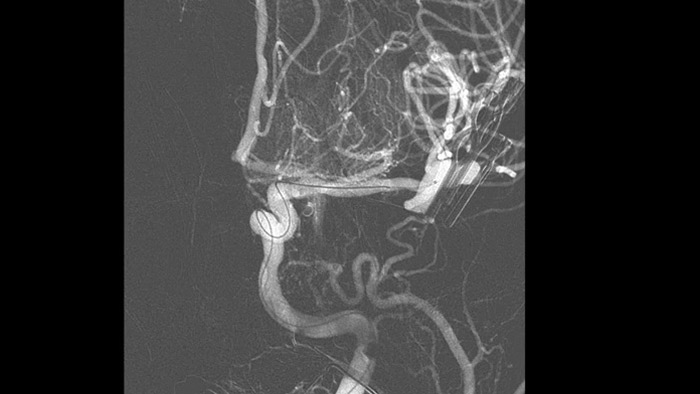

Aprimore a visualização de stents endovasculares, desviadores de fluxo e outros dispositivos e também a morfologia do vaso até o nível perfurador com o SmartCT Vaso. Essa técnica de aquisição, baseada em uma varredura de TC de Feixe Cônico e uma injeção de contraste intra-arterial, é cada vez mais utilizada para o acompanhamento de aneurismas tratados com stents desviadores de fluxo para verificar o posicionamento do dispositivo.